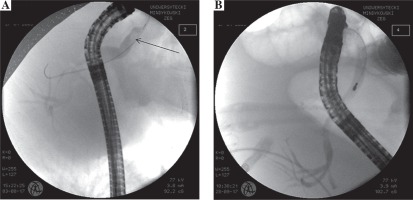

At day +35 she complained of acute abdominal pain accompanied by significant elevation of gamma glutamyl transpeptidase (3673 U/l), alkaline phosphatase activity (643 U/l) and a total and conjugated bilirubin level (5.17 mg/dl and 4.15 mg/dl, respectively). On magnetic resonance (MRI) cholangiopancreatography, the common bile duct (CBD) was widened with a diameter of 6 mm and in the distal part of CBD there were bile deposits of 5 × 3 mm size. She was qualified to urgent endoscopic retrograde cholangiopancreatography (ERCP). After sphincterotomy, removal of bile deposits was carried on with endoscopic basket. Additionally a 5 cm 7F prosthesis was inserted into the distal CBD (Fig. 2).

Fig. 2

ERCP showing a common bile duct (day +35): A) mildly dilated duct with biliary stone (black arrow) before extraction, B) with no signs of dilation after stone extraction (6 weeks later)